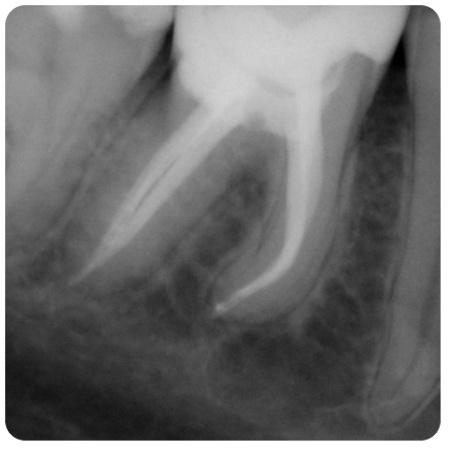

Aby osiągnąć taki efekt, musieliśmy przeprowadzić ekstrakcję złamanej górnej jedynki i w jej miejsce jednoczasowo wszczepić implant, a następnie na pozostałe zęby wykonać licówki i korony pełnoceramiczne w najjaśniejszym odcieniu.

Całość została zaprojektowana w harmonii z twarzą i rodzajem uśmiechu naszej Pacjentki. Leczenie trwało 3 miesiące.

Wykonał je lek.stom. Michał Badowski we współpracy z laboratorium Dentalscan (tech.dent. Joanna Gancarz).